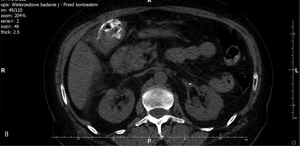

63-letnią kobietę przyjęto na oddział chirurgiczny z przewlekłymi bólami brzucha nasilającymi się w ostatnich 3 tygodniach. Od tygodnia obserwowano zażółcenie powłok, wymioty, odbarwienie stolca i brak łaknienia, co sugerowało żółtaczkę mechaniczną. W ciągu ostatnich 2 miesięcy masa ciała pacjentki zmniejszyła się o 8 kg. Na podstawie wcześniejszych badań USG, wykonanych 10 i 12 lat temu, rozpoznano u niej kamicę pęcherzyka żółciowego. Żółtaczkę potwierdzono w badaniach laboratoryjnych. Wykazano w nich także leukocytozę oraz podwyższone stężenie dimera D i CRP. W wykonanym przy przyjęciu badaniu USG zaobserwowano liczne złogi w pęcherzyku żółciowym i pogrubienie jego ściany z nieregularnym hiperechogenicznym naciekiem w sąsiadującym miąższu wątroby. Stwierdzono także poszerzenie dróg żółciowych wewnątrzwątrobowych w obrębie prawego płata oraz obecność niewielkiej ilości wolnego płynu w jamie otrzewnej (ryc. 1A, B). W dnie pęcherzyka uwidoczniono silne echo zlokalizowane w zarysie ściany narządu (ryc. 1C).

Wszystkie przedstawione warianty rozpoznania są prawdopodobne. Obraz USG z ryciny 1C sugeruje obecność złogu poza obrysem zmienionego zapalnie pęcherzyka żółciowego (rozpoznanie kamicy jest oczywiste na podstawie wcześniejszych obrazów). Bezdyskusyjne jest także rozpoznanie rozległego nacieku, prawdopodobnie zapalnego, w ścianie i w sąsiedztwie pęcherzyka. Fakt ten mocno uprawdopodabnia wytworzenie odleżyny w dnie pęcherzyka, perforacja jego ściany i migracja złogu do jamy otrzewnej.